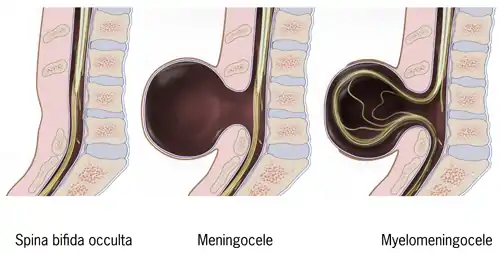

Spina bifida is a birth defect in which there is incomplete closing of the spine and the membranes around the spinal cord during early development in pregnancy.[1] There are three main types: spina bifida occulta, meningocele and myelomeningocele.[1] The most common location is the lower back, but in rare cases it may be in the middle back or neck.[9] Occulta has no or only mild signs, which may include a hairy patch, dimple, dark spot or swelling on the back at the site of the gap in the spine.[5][1] Meningocele typically causes mild problems, with a sac of fluid present at the gap in the spine.[1] Myelomeningocele, also known as open spina bifida, is the most severe form.[2] Problems associated with this form include poor ability to walk, impaired bladder or bowel control, accumulation of fluid in the brain (hydrocephalus), a tethered spinal cord and latex allergy.[2] Learning problems are relatively uncommon.[2]

There are two types: spina bifida occulta and spina bifida cystica.[16] Spina bifida cystica can then be broken down into meningocele and myelomeningocele.[16]

Occulta is Latin for "hidden". This is the mildest form of spina bifida.[17] In occulta, the outer part of some of the vertebrae is not completely closed.[18] The splits in the vertebrae are so small that the spinal cord does not protrude. The skin at the site of the lesion may be normal, or it may have some hair growing from it; there may be a dimple in the skin, or a birthmark.[19] Unlike most other types of neural tube defects, spina bifida occulta is not associated with increased AFP, a common screening tool used to detect neural tube defects in utero. This is because, unlike most of the other neural tube defects, the dural lining is maintained.

A posterior meningocele (/mɪˈnɪŋɡəˌsiːl/) or meningeal cyst (/mɪˈnɪndʒiəl/) is the least common form of spina bifida. In this form, a single developmental defect allows the meninges to herniate between the vertebrae. As the nervous system remains undamaged, individuals with meningocele are unlikely to suffer long-term health problems, although cases of tethered cord have been reported. Causes of meningocele include teratoma and other tumors of the sacrococcyx and of the presacral space, and Currarino syndrome.

Myelomeningocele (MMC), also known as meningomyelocele, is the type of spina bifida that often results in the most severe complications and affects the meninges and nerves.[27] In individuals with myelomeningocele, the unfused portion of the spinal column allows the spinal cord to protrude through an opening. Myelomeningocele occurs in the third week of embryonic development, during neural tube pore closure. MMC is a failure of this to occur completely.[3] The meningeal membranes that cover the spinal cord also protrude through the opening, forming a sac enclosing the spinal elements, such as meninges, cerebrospinal fluid, and parts of the spinal cord and nerve roots.[28] Myelomeningocele is also associated with Arnold–Chiari malformation, necessitating a VP shunt placement.[10]